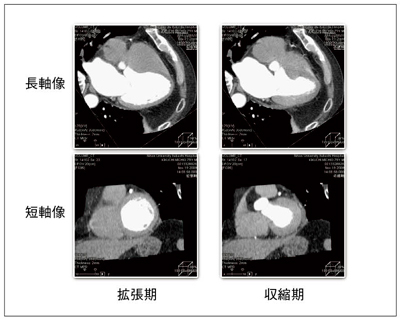

ManualによるCT心機能解析では,長軸像および短軸像ともに拡張期,収縮期を視覚的に判断し,設定することにより左室拡張末期容積(EDV),左室収縮末期容積(ESV),左室駆出率 (EF)を算出した(図3)。AutoによるCT心機能解析では,1心拍を10%ごとに10フェーズに分割し,これから得られるtime-volume curveからEDV,ESV,EFを自動算出した(図4)。ザイオソフト社製のソフトウェアでは,10フェーズの画像を取り込み,全フェーズ解析のボタンをワンクリックするだけで,十数秒程度で容易に心機能指標の自動算出が可能であった(図5)。自動解析にて得られる心機能指標はEDV,ESV,EFの ほか,身長,体重の入力によりCO,CI,PFR,PERなどのパラメータも算出可能であった。(図6)。

図3 320列CTによる心機能解析(Manual)